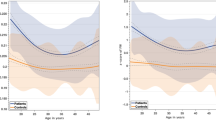

To assess the phase shift between WD patients and healthy subjects, we analyzed all the 23 WD patients recruited and 23 age- and sex-matched healthy controls. The results showed all the phase value data measured from regions of interests of WD patients were lower than those of control subjects ( Table 2 , Figure 2 ), and significantly negative phase shift was found in bilateral putamen (PU) (left P = 0.009, right P = 0.001), CA (left P = 0.001, right P = 0.001), thalamus (TH) (left P < 0.001, right P < 0.001), red nucleus (RN) (left P = 0.031, right P = 0.049) and SN (left P = 0.003, right P = 0.047) ( Figure 2 ). There is no significant difference in left and right globus pallidus (GP) (left P = 0.372, right P = 0.130).

Phase shift of bilateral regions of interest (ROIs) between Wilson’s disease (WD) and healthy controls (HC). Black column corresponds to the mean phase value of WD patient (n = 23) and white column corresponds to the mean phase value of healthy controls (n = 23). Differences of phase shift of ROIs between WD and healthy controls are analyzed using Mann–Whitney U-tests, and significant differences are indicated with * (P < 0.05), ** (P < 0.005).

Phase Shift Between Different Symptom Groups

Among the 23 patients with WD, 16 patients originated with neurological manifestations, 5 with hepatic manifestations. In order to probe whether different symptoms related with different phase values in different regions, we analyzed our data according to different symptoms. The results showed that, in most of brain region measured, the phase value of neurological WD patients were higher than that of hepatic WD patients ( Table 1 , Figure 3 ), and there was significant lower negative phase value in bilateral PU (left, P = 0.025; right, P = 0.002) and bilateral TH (left, P = 0.025; right, P = 0.025) of neurological WD patients, compared with hepatic WD patients.

Phase value difference between neurological Wilson’s disease (WD) patients and hepatic WD patients. Black column corresponds to the mean phase value of neurological WD patients (n = 16) and white column corresponds to the mean phase value of hepatic WD patients (n = 5). Differences of phase shift of regions of interest (ROIs) between WD and healthy controls are analyzed using Mann–Whitney U-tests, and significant differences are indicated with * (P < 0.05), ** (P < 0.005).